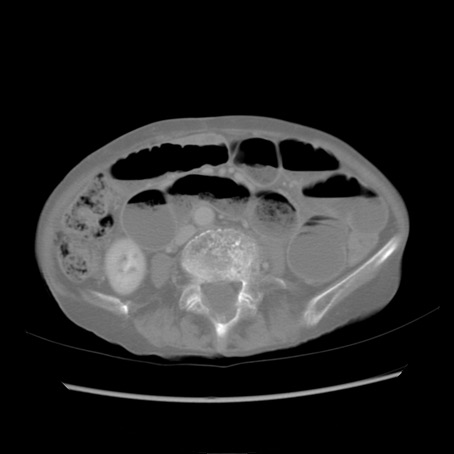

症例25(横断像)

【症例】80歳代女性

【主訴】胸のつかえ感

【現病歴】約9時間前に食後から胸のつかえた感じあり、嘔吐あり、来院。

【既往歴】胃癌(全摘)、胆摘、虫垂炎

【身体所見】心窩部に圧痛あり、反跳痛なし。

【データ】WBC 5700、CRP 0.05